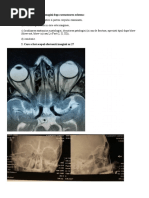

Corelarea examenului neurologic cu aspectele imagistice